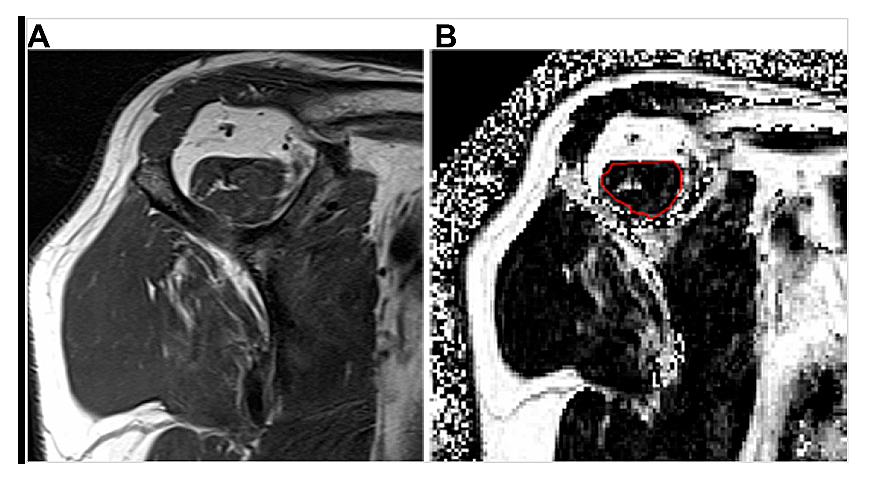

Imaging is central for establishing the clinical diagnosis and prognosis for patients presenting with either traumatic acute-onset shoulder dysfunction or non-traumatic shoulder disorders which are not self-limited [22,44,45]. Magnetic resonance imaging (MRI) is the leading imaging modality in the United States to provide definitive imaging evaluation of patients with symptomatic shoulder dysfunction and is a valid and reliable method for diagnosing and characterizing the pattern of RC tear (Figure 1) [20,42,46–48]. MRI also provides concurrent prognostic information about the degree of intramuscular fatty infiltration associated with RC tear, a critical factor that influences orthopaedic surgeons’ clinical decision-making regarding patients’ eligibility to receive RC repair (RCR) surgery (Figure 2) [20,42,46–50]. RC tear is associated with structural changes in the corresponding muscle belly related to intramuscular proliferation of adipose cells and inflammation, fibrosis and apoptosis of myofibers leading to global muscle atrophy and dysfunction [51–53]. Animal and human models of RC tear show that intramuscular fatty infiltration is inversely related to muscular contractile force at the rotator cuff and does not improve after RCR surgery [20,51,54]. During initial steps of pre-operative evaluation, imaging metrics of RC muscle quality are critical, as advanced RC intramuscular fatty infiltration is a relative contraindication to RCR surgery and is associated with poor postsurgical outcomes [46,48–50].

FIGURE 2

Figure 2. Examples of rotator cuff muscle fatty infiltration classification on magnetic resonance imaging (MRI). (A) Oblique sagittal T1-weighted MRI shows a supraspinatus muscle with streaks of internal fat, consistent with semi-quantitative Goutallier grade 1 fatty infiltration. (B) Quantitative oblique sagittal 6-point Dixon fat fraction map MRI following manual image segmentation calculates an amount of 10.5% supraspinatus muscle fatty infiltration within the region of interest (red circle).